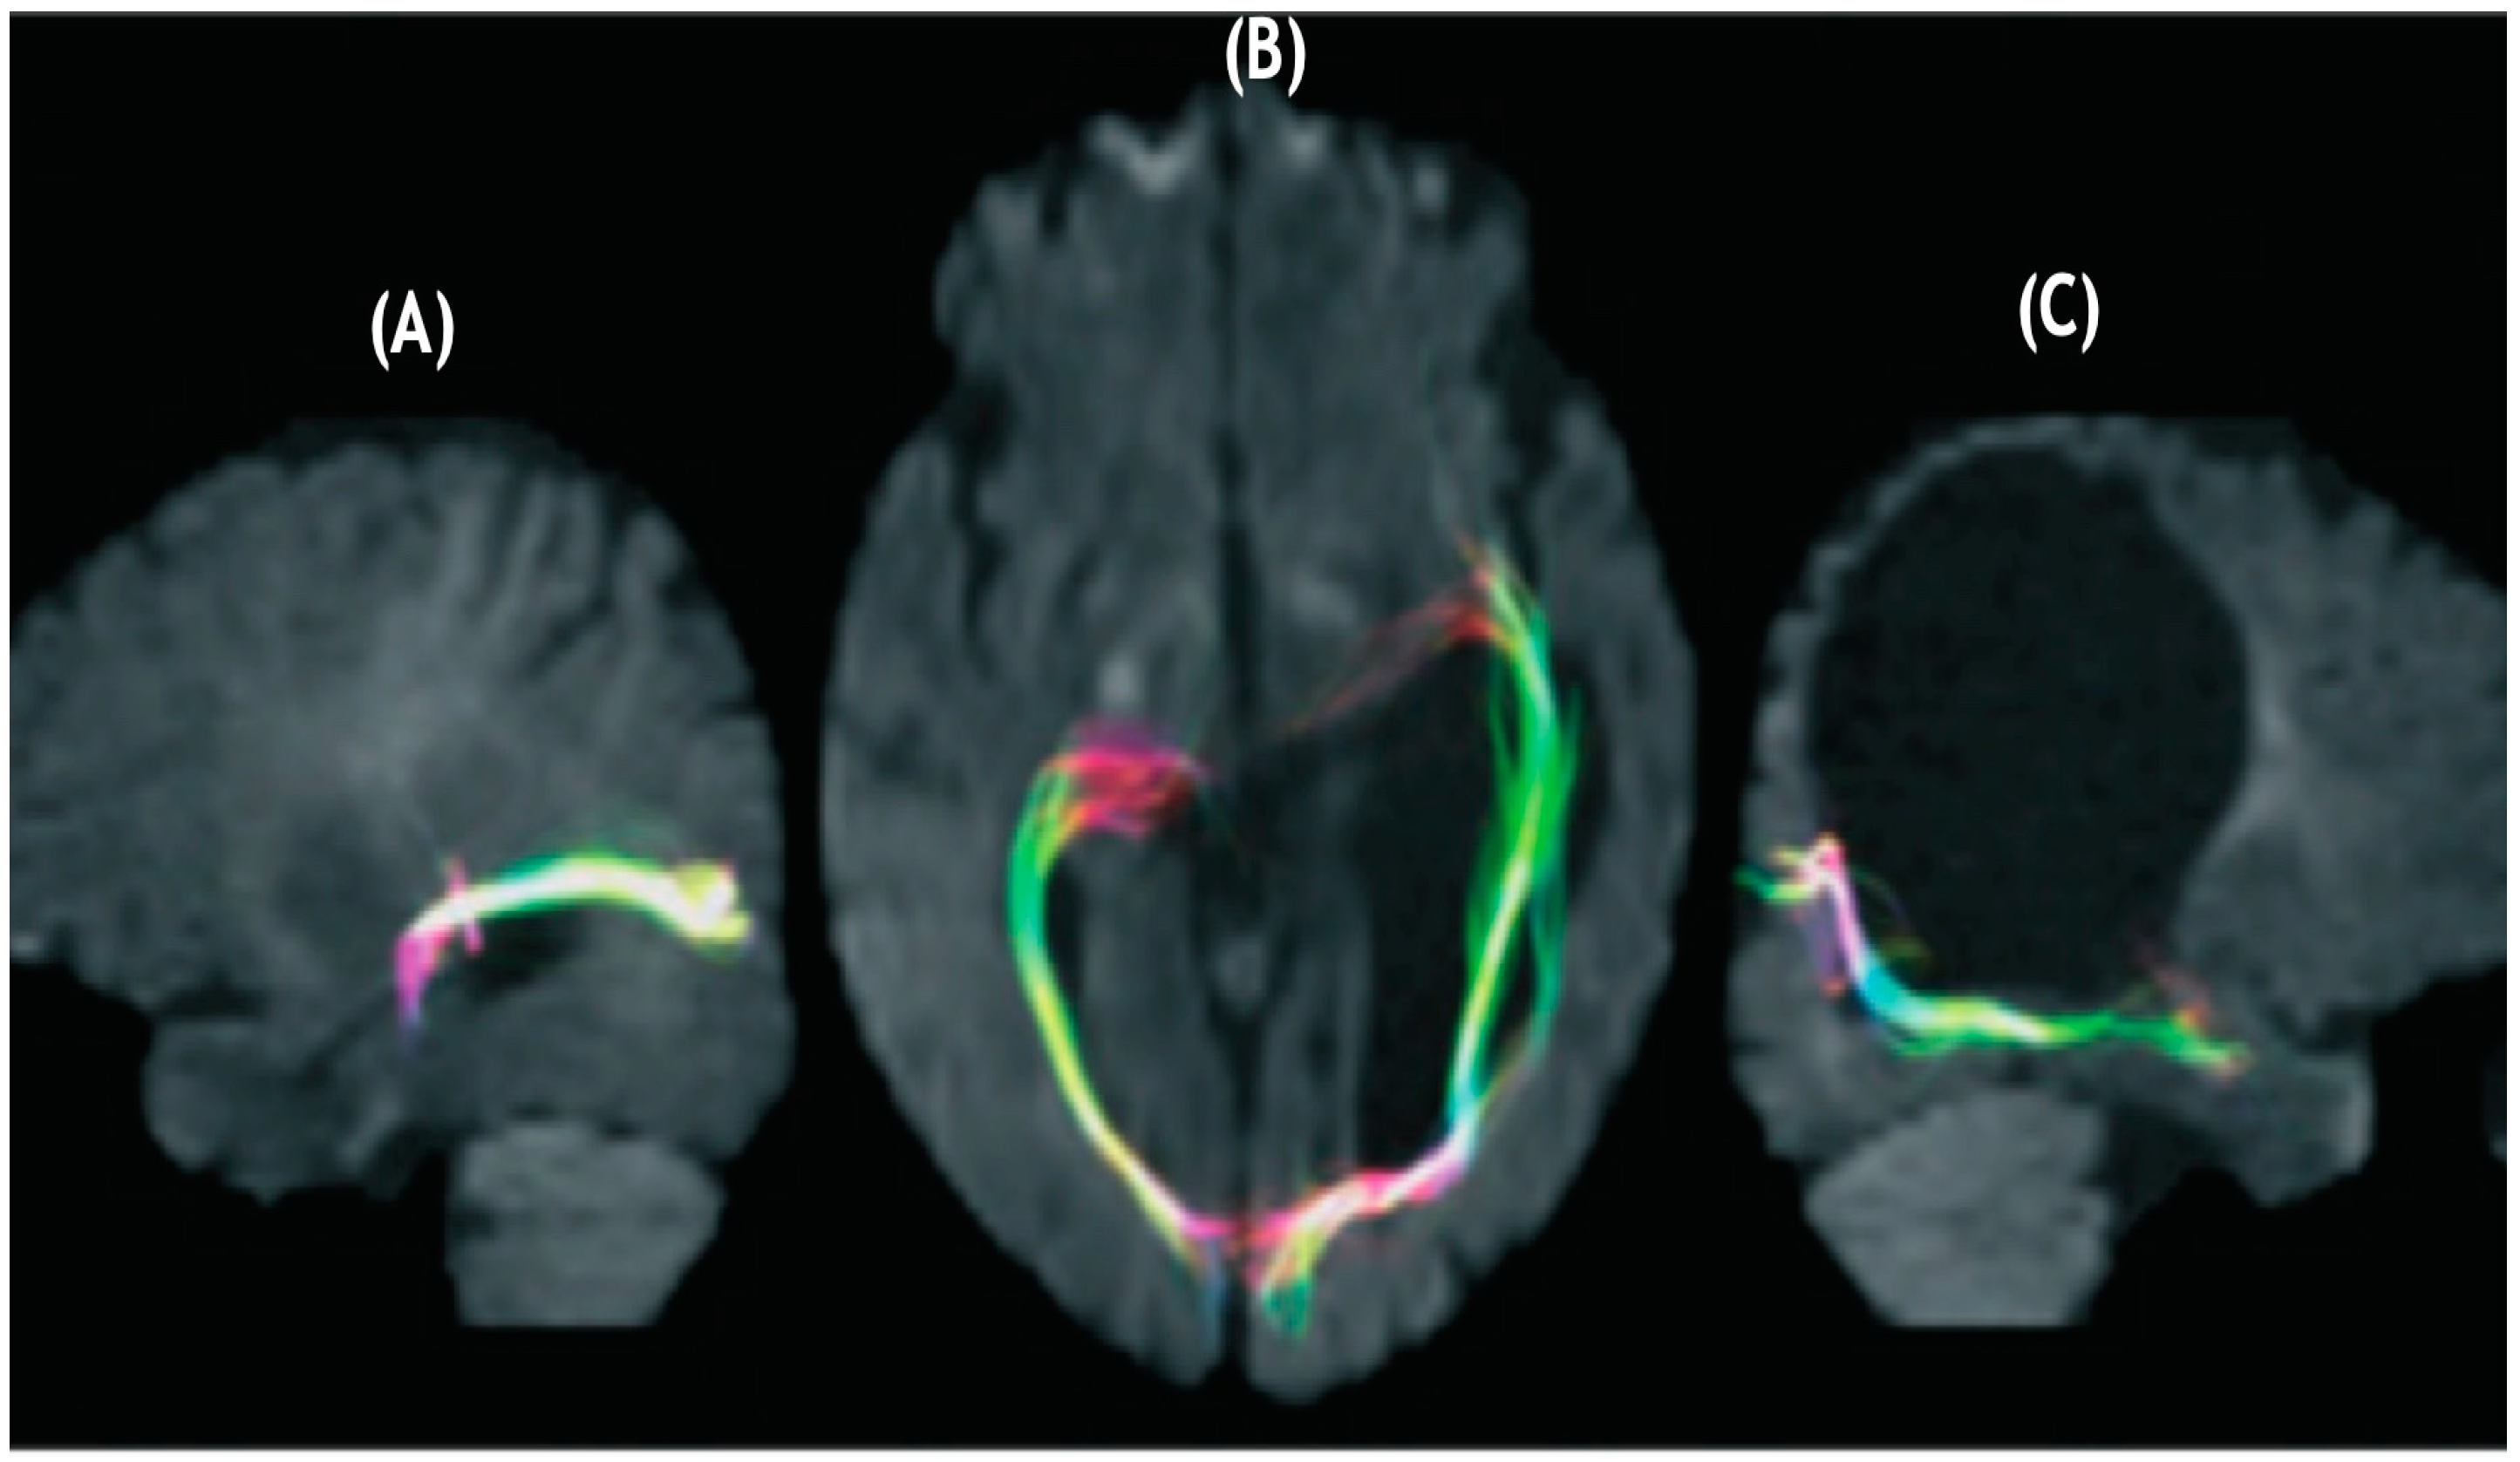

Guzzetta and colleagues [55] found support for the notion that infants with preterm unilateral lesions in periventricular white matter regions that occurred early in the third trimester of pregnancy, evidenced normal visual fields independent of the fact that a significant lesion was evidenced in the left periventricular region where the optic radiations should have been found. Their findings in their case are reproduced in Figure 1.

Figure 1.

Diffusion tensor tractography of (A) optic radiations of left hemisphere evidencing a pathway avoiding an enlarged left ventricle projecting to the calcarine cortex. (B) bilateral optic radiations with the fibers of the left hemisphere proceeding laterally and anteriorly in contradistinction to the non-lesioned hemisphere. (C) Optic radiations of the right hemisphere appear to follow a normal trajectory (after Guzzetta et al. [56] with permission).

Numerous investigators [57,58,59,60,61,62,63,64,65,66] have supported the notion that preterm infants having sustained lesions in periventricular white matter evidenced somatosensory projections that found alternate routes that provided linkages with the postcentral gyrus. Guzzetta et al. [56] reported on a patient demonstrating normal visual fields despite the existence of a lesion of the left periventricular white matter involving most of the tissue where optic radiations would normally sit (as described in Figure 1). These investigators demonstrated, through diffusion tensor tractography, how optic radiations possessed projections that deviated away from the affected area and instead bypassed a cystic lesion eventually connecting with the occipital cortex. In addition to the N = 1 report of Guzzetta and colleagues [55], post-mortem support for the notion of rerouting during the last trimester of pregnancy is supported by Hevner [59] and others in animal studies [60,61,62,63,64,65].